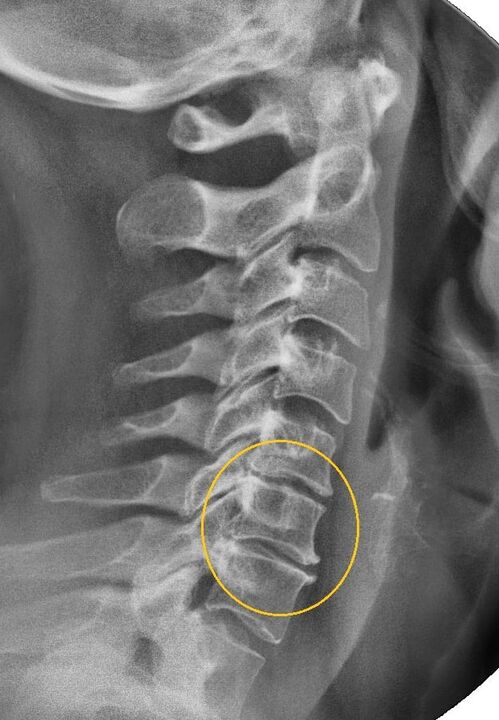

The most informative diagnostic procedure is x-ray.1st degree pathologies correspond to the 1st or 2nd radiological stage.The resulting images show typical signs of the disease.

| Radiological stages of first degree cervical osteochondrosis. | Characteristic signs |

|---|---|

| Stage 1 | Minor changes in the curvature of the spine in the cervical region, affecting one or more segments. |

| Stage 2 | Slight thickening of the intervertebral discs, deformation of the uncinate processes, straightening of the lordosis, minor growths of bone structures. |